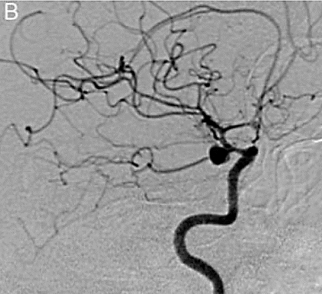

Paciente, 38 anos, admitida em pronto socorro com queixa de cefaleia súbita, associada a visão dupla e vômitos. Submetida a tomografia de crânio sem contraste com a presença de hemorragia subaracnoidea. Encaminhada para o serviço de hemodinâmica para angiografia de vasos cerebrais (figura 5).

Figura 5 Arteriografia cerebral